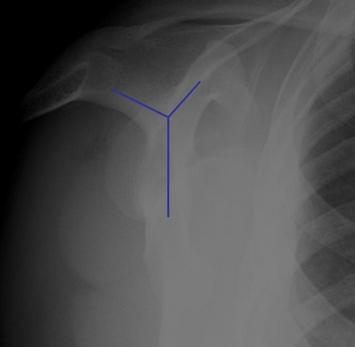

4. Scapular Y lateral view

acromion이 보이긴 보입니다.